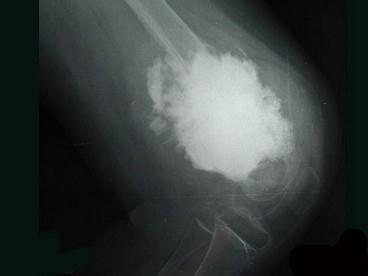

问题 女,10岁,左大腿疼痛,夜间加重,肿胀明显,请结合影像图像,最可能的诊断是 ( )

选项 A、骨化性肌炎 B、以上都不正确 C、化脓性骨髓炎 D、骨肉瘤 E、成骨性骨转移

答案 D